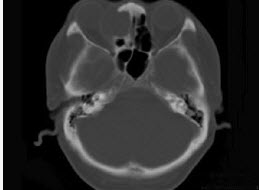

- 多项选择题女性38岁,右侧眼球运动障碍伴眼球突出4个多月,CT扫描如图,请选择正确的描述和答案()。

A、右侧筛窦内可见囊性肿块影,边缘光整

B、囊性肿块向右侧眼眶内突入,压迫内直肌

C、右侧眶内壁呈受压变薄、断裂

D、考虑为右侧筛窦黏液囊肿

E、考虑为筛窦癌

- A,B,C,D